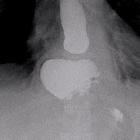

Postoperative

herniation of Nissen fundoplication. Upper gastrointestinal series demonstrated a filiform pass of barium along the distal oesophagus at the level of the structure, with slight dilatation of the proximal portion.